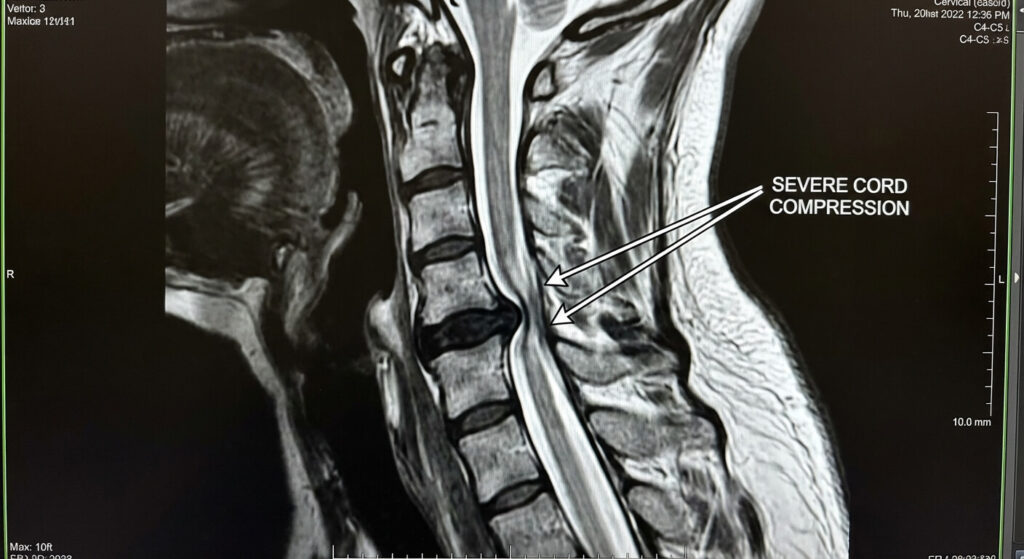

L’arthrose cervicale est banale après 50 ans, mais la myélopathie est sa complication la plus sévère. Le canal rachidien (le tunnel osseux dans lequel passe la moelle épinière) devient trop étroit (sténose). La moelle souffre.

Sans décompression chirurgicale rapide (laminectomie), la destruction nerveuse continue jusqu’à la paralysie (tétraparésie). Même après l’opération, si la moelle a trop souffert, des séquelles motrices définitives persistent. C’est sur ces séquelles que le dossier MDPH prend tout son sens.